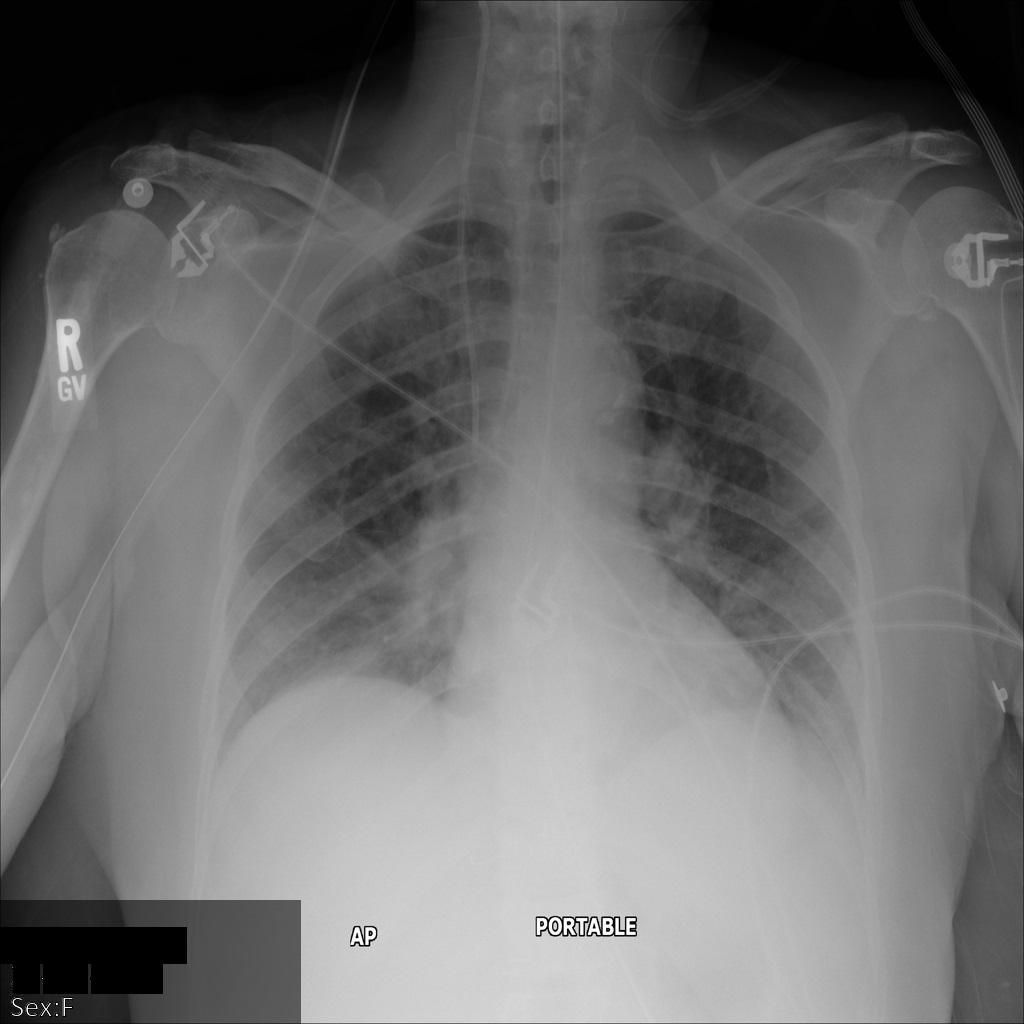

En la siguiente imagen se muestra una radiografía de un paciente sin censurar:

Después de enviar la imagen a la API Cloud Healthcare mediante la opción REDACT_SENSITIVE_TEXT, la imagen se muestra de la siguiente manera:

Puedes ver que ha ocurrido lo siguiente:

- El

PERSON_NAMEde la parte inferior izquierda de la imagen se ha ocultado - El

DATEde la parte inferior izquierda de la imagen se ha ocultado

El sexo del paciente no se ha ocultado porque no se considera texto sensible según los infoTipos DICOM predeterminados.